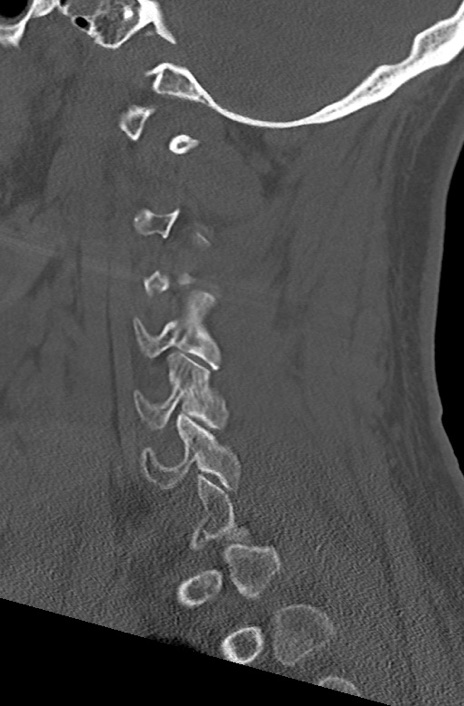

頚椎CT

矢状断像と横断像